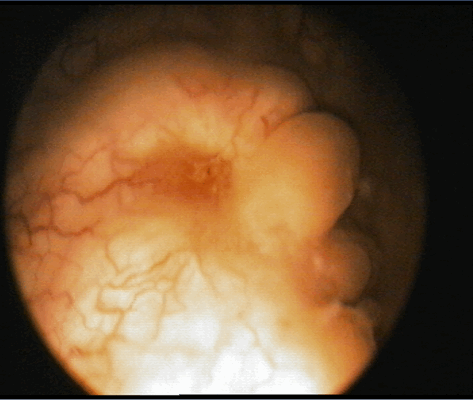

Цистоскопическое обследование пациентки О.

Цистоскопическая картина солидного образования

Цистоскопическое обследование пациента М.

Цистоскопическая картина солидного образования, вдающегося в полость мочевого пузыря в виде массивных бугристых масс, покрытых отечной слизистой оболочкой с очагами кровоизлияний, с явлениями распада и инкрустации солями

По данным ультрасонографии ретенционные изменения верхних мочевых путей с обеих сторон были выявлены у пациентки О., 35 лет, (чашечки и лоханка справа 16 и 32 мм, слева – 15 и 35 мм соответственно, у остальных пиелокаликоэктазии не было. Больным была выполнена цистоскопия, по данным которой в 3 случаях определялось стелящееся солидное образование в диаметре около 8 см (пациентка О., 35 лет), 5,6 (пациент М., 43 лет) и 2,8 см (пациент С., 56 лет) с явлениями буллезного отека, распада, кровоизлияний и инкрустацией мочевыми солями Образования предположительно характеризовались инфильтративным характером роста.